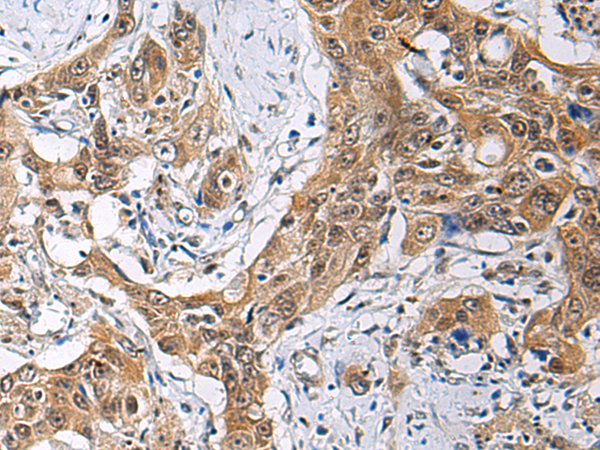

分类: 科研抗体货号: P10402别名: Dgt6; FAM29A应用: IHC反应种属: Human